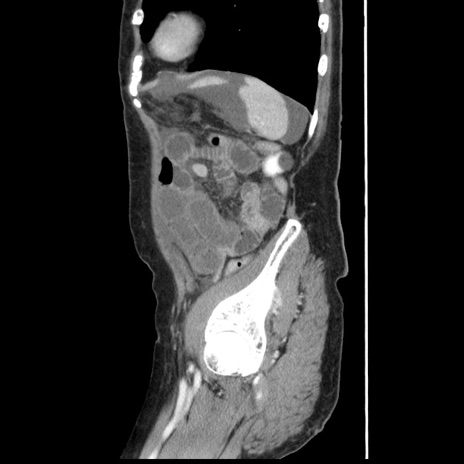

横断像

冠状断像